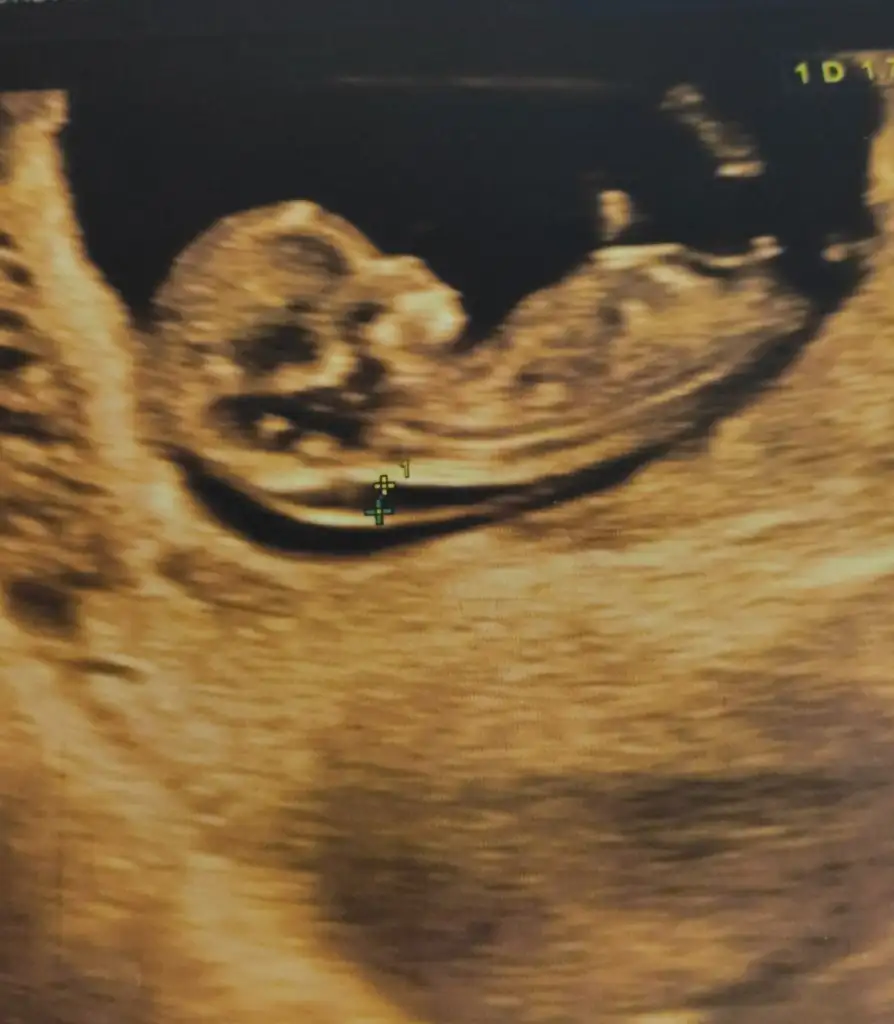

Merhabalar anlayanlar benim görüntülerede bakabilirmi 13 haftalık olduk merak ediyorum 😉

• IMG20200423112010.webp

• IMG20200422153547.webp